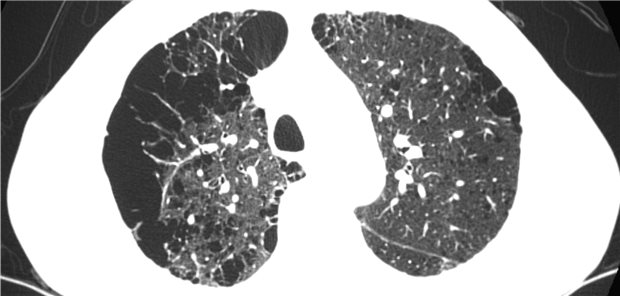

In der Diagnostik der COVID-19-Pneumonie nimmt die Computertomografie des Thorax eine herausragende Position ein. Das wird ein weiteres Mal durch eine Studie aus China belegt.